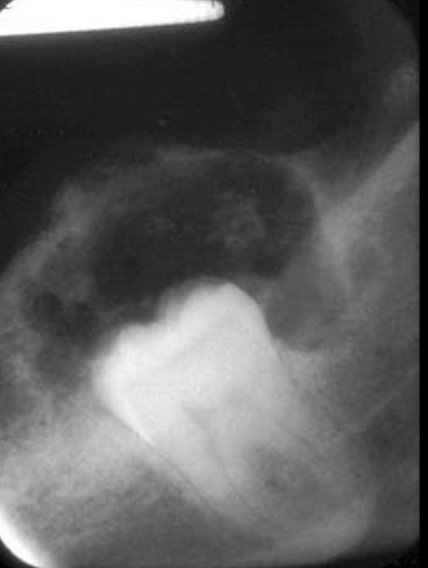

describe what’s occurring in this radiograph

pericoronal/mural; impacted tooth

displacement of #32 + IAN

osseous expansion

thinning of cortices